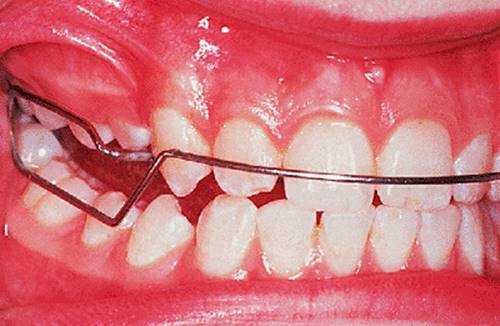

Before discussing functional appliances in detail, Fig. 18.1 gives an overview of this type of functional appliance in clinical use. This patient has a Class II division 1 malocclusion of the type for which functional appliances are very suitable, and for which they have been used for many years.

There are a number of important features to note which will be discussed further later in the chapter. First, the patient is still growing and the signs are that her pattern of facial growth is likely to be favourable. Although the skeletal pattern is Class II, the vertical relationships are close to average and the direction of mandibular growth is likely to be a mild forward rotation (see Chapter 4) which is favourable to the correction of a Class II malocclusion. Second, the soft tissue morphology is favourable despite the lips being incompetent, with the lower lip resting behind the upper incisors. The lower lip line is above the level of the upper incisal edges, and after the overjet has been reduced the lower lip will rest labially to the upper incisors, so helping to resist any tendency for relapse of the overjet. Third, the arches are well aligned — functional appliances have no mechanism for treating irregularities of alignment of the teeth.

The appliance holds the mandible in a forward postured position, in this case with the incisors edge to edge (Fig. 18.1(f)). The facial musculature is thus stretched, and applies a posterior force to the upper arch and an anterior force to the lower arch. The lower incisors have acrylic capping to prevent excessive labial tilting of the lower incisors, and this also serves as a bite-plane to reduce the overbite (Chapter 10). The appliance must be worn for at least 14–16 hours each day, but once the overjet has been reduced fully the amount of daily wear can gradually be reduced to sleeping hours only. The patient should continue to wear the appliance overnight in this way as a retainer, at least until the period of rapid pubertal growth is complete. Figures 18.1(g) and 18.1(h) show the dental and facial changes which occurred during treatment.

Fig. 18.1. (a) This 12-year-old girl had a skeletal II facial pattern and average facial proportions. The lips were incompetent with the lower lip lying below the upper incisors at rest. (b), (c) She had a Class II division 1 malocclusion with an overjet of 10 mm, the overbite was increased and complete, and the molar relationship was Class II on both sides. (d), (e) The upper and lower arches were well aligned. (f) A functional appliance (an activator) was fitted. (g) The corrected occlusion with Class I incisor and molar relationships. (h) The patient's facial profile at the end of treatment.